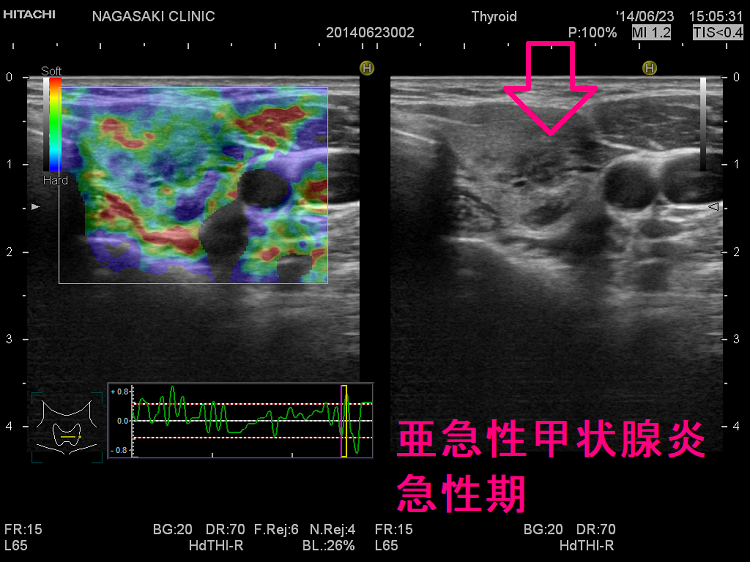

下は亜急性甲状腺炎の超音波(エコー)画像で、炎症の強い部分は黒く、エラストグラフィーでは青くなります。